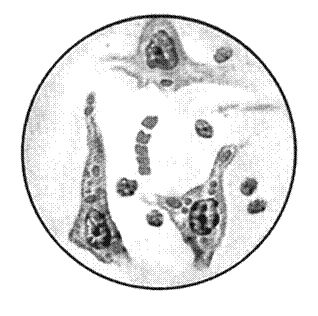

Легче при вирусных инфекциях выявить внутриклеточные включения (рисунок 8).

Рисунок 8 –Вирусные включения:

1 – тельца Гуарниери в клетке, зараженной вирусом оспы; 2 – включения в цилиндрическом эпителии, зараженном вирусом гриппа; 3 – включения в эпителии, зараженном реовирусом; 4 – тельца Бабеша-Негри в нейроцитах; 5,6 – внутриядерные включения в эпителии, зараженном герпес- и аденовирусом; 7 – внутриядерные и цитоплазматические включения в эпителии, зараженном вирусом кори

В основном они представлены скоплениями вирионов вперемешку с реактивными клеточными продуктами и в зависимости от места репликации вирионов находятся в цитоплазме или ядре клеток-хозяев. В частности, цитоплазматическими включениями являются тельца Гуарниери в эпителиальных клетках, скопления реовирусов и вирусов гриппа в них, тельца Бабеша-Негри – в нейроцитах. Ядерные адено-, папова- и герпесвирусные включения состоят из клеточного материала. Изредка в одной и той же клетке вирусы, например, коревой, формируют цитоплазматические и ядерные включения.

По форме, размерам, структуре, отношению к красителям вирусные включения строго специфичны. Например, тельца Гуарниери имеют округлую, серповидную или амебоидную форму диаметром 1–10 мкм, тельца Бабеша-Негри – овальные или эллипсоидные, достигающие 20 мкм, включения реовирусов серповидные, наполовину охватывающие клеточное ядро, коревые включения – в виде почкующихся мелких дрожжей (рисунок 9).